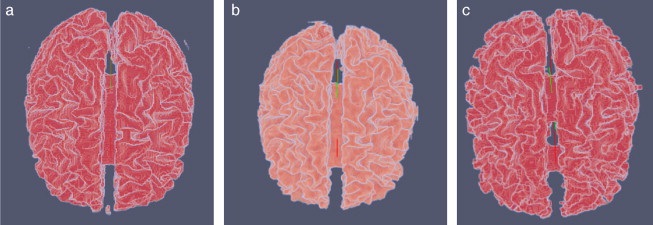

En la figura 26 son presentados las vistas tridimensional del volumen de la zona de la materia blanca proporcionado por BrainWeb, el volumen obtenido con Region Growing y volumen obtenido con Watershed.

Vista volumétrica de la zona de la materia blanca. (a) Volumen original de la ...

Figura 26.

Vista volumétrica de la zona de la materia blanca. (a) Volumen original de la materia blanca proporcionado por BrainWeb. (b) Vista 3D del volumen obtenido con Region Growing en la figura 26 .d. (c) Vista 3D del volumen obtenido con Watershed en la figura 27 .b.